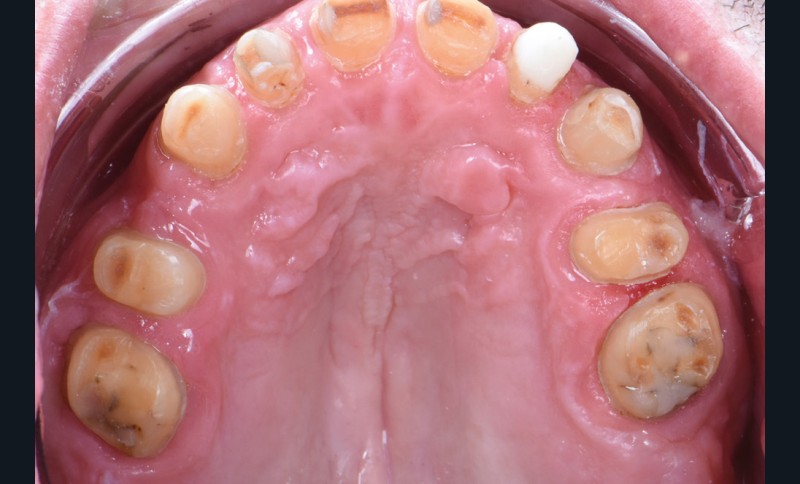

Au vu du contexte para-fonctionnel et de l’étendue de la perte tissulaire, des coiffes périphériques minimalement invasives ont été choisies afin de restaurer l’esthétique et la fonction. Actuellement, aucun consensus n’est fait sur le choix du matériau d’infrastructure à privilégier. Les matériaux hybrides usinables présentent des propriétés mécaniques, physiques et biologiques intéressantes en contexte d’usure sévère (e.g., module d’élasticité, résistance à la propagation de fêlures, facilité de réintervention). Une réhabilitation globale avec remontée de dimension verticale d’occlusion (DVO) par l’intermédiaire de coiffes composites renforcés en nano-céramiques est décrite.